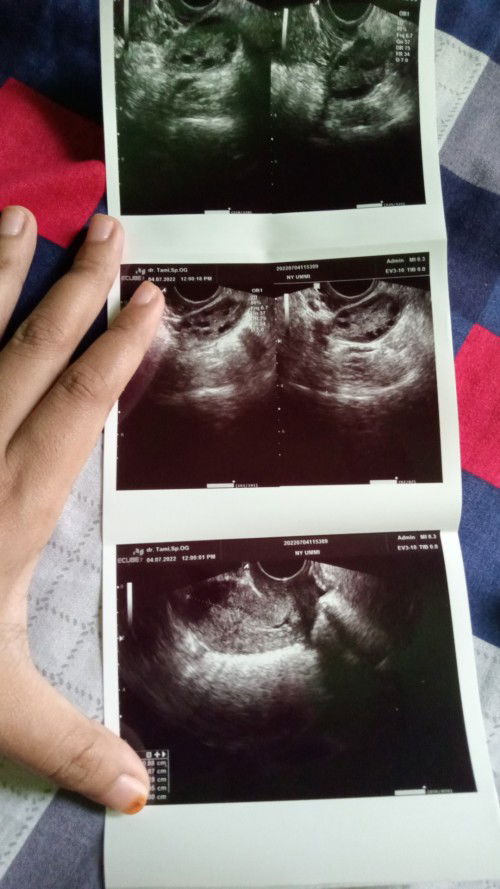

Saya kemarin USG dan hasilnya begini, padahal saya sudah telat 4 bulan?

Apakah bunda ada yang bisa membaca hasil usg saya ini?

Itu PCOS bunda.. Salah satu ciri² yg mngalami PCOS haidnya tdk teratur bahkan smpe bulanan.. Jadi, telat haid dlm waktu lama bukan berarti psitif hamil bund.. Obgynnya ngga kasih info apa² ke bunda..?? trus bliau resepin apa bun..?

Baca lagibun maaf sebelumnya, itu usg nya mirip kaya saya dulu juga gitu. namanya PCOS bun. sel telurnya kecil2 dan banyak tp tidak ada yg bisa dibuahi sama sperma. biasanya sama dr nya dikasih obat untuk perbaiki haid bun

itu kayaknya sel telurnya kecil2 ya bun, biasanya itu penyebab haid tidak teratur, coba bunda rutinin olahraga dan kurangi makanan/minuman manis (diet gula)